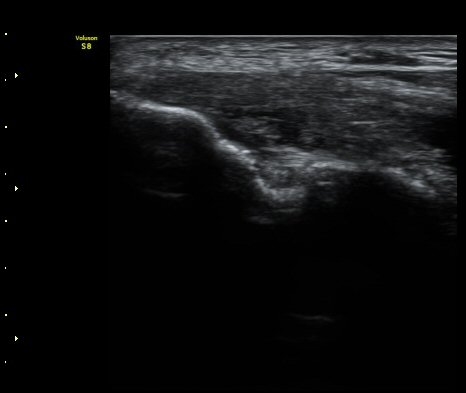

ÃÊÀ½ÆÄ °Ë»ç

³»»ó°ú¿¡¼­ ¼Õ¸ñ±¼°î°Ç Á¾´Ü¸é°Ë»ç»ó ³»¤µ¾Æ°ú ÇÇÁú°ñÀÇ ºÒ±ÔÄ¢º¯È­¿Í ÈûÁÙ³» ¿¬°á¼º

¼Ò½Ç ¹× Àü¹ÝÀûÀÎ Àú¿¡ÄÚ ºÎÁ¾ÀÌ °üÂûµÈ´Ù(±×¸² 1, 2, 3). ±¼°î°Ç ÀϺδ Á¤»óÀûÀÎ °í¿¡ÄÚ

¼¶À¯ ¾ç»óÀ¸·Î °üÂûµÈ´Ù(±×¸² 4). ÈûÁ٠Ⱦ´Ü¸é °Ë»ç¿¡¼­µµ °Ç³» ¿¬°á¼º ¼Ò½Ç°ú Àú¿¡ÄÚ

º¯È­°¡ °üÂûµÈ´Ù(±×¸² 5).  ÃÊÀ½ÆÄÀ¯µµÇÏ ÁÖ»ç ½Ã ÁÖ»ç¾×ÀÌ °Ç³»¿¡¼­ ÀÚÀ¯·Ó°Ô ÆÛÁ®¼­

°ÇÀÇ ½ÉÇÑ ÆÄ¿­À» º¸¿©ÁØ´Ù(÷ºÎ ÆÄÀÏ µ¿¿µ»ó 1).